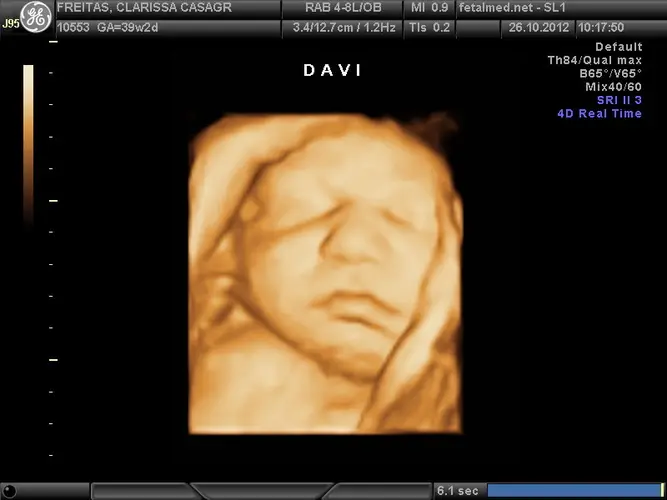

Nesta semana, seu bebê já está praticamente pronto para vir ao mundo! O crescimento em tamanho e peso desacelerou significativamente, o que é um alívio para suas costas doloridas e sua pele já tão esticada. Embora não haja grandes mudanças físicas, o desenvolvimento interno continua a todo vapor, especialmente o cérebro, que cresce e se desenvolve rapidamente – um ritmo que se manterá acelerado durante os primeiros três anos de vida.

A maior parte do vérnix caseoso (aquela substância esbranquiçada que protegia a pele) já desapareceu, e a pele do bebê adquiriu uma tonalidade mais rosada ou esbranquiçada, independentemente de qual será sua cor definitiva após o nascimento. O crânio ainda mantém uma flexibilidade estratégica – as cinco fontanelas (conhecidas como moleiras) permanecem abertas e podem se comprimir umas contra as outras durante o parto, facilitando a passagem pelo canal de parto sem causar danos ao cérebro.

Os pulmões estão completamente maduros e a produção de surfactante – substância essencial para manter os alvéolos abertos – está no seu pico. O tórax apresenta-se mais proeminente, e o abdome permanece grande e arredondado, principalmente devido ao fígado, que ainda produz glóbulos vermelhos. Os olhos ainda não possuem os ductos lacrimais completamente formados, que só aparecerão algumas semanas após o nascimento.